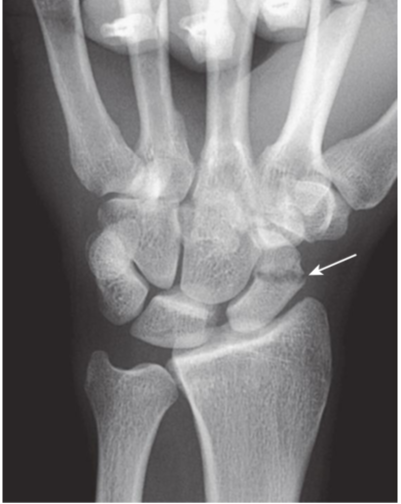

Avascular necrosis of the proximal pole of the scaphoid.

A close-up frontal view of the wrist demonstrates that the proximal pole of the scaphoid (black arrow)is denser than the distal pole (solid white arrow). There is a fracture through the waist of the scaphoid (dotted white arrow). Because of the peculiar blood supply of the scaphoid (from distal to proximal), fractures through the wrist may interrupt the proximal blood supply while the remainder of the bones of the wrist, having normal blood supply, become demineralized. This makes the proximal pole of the scaphoid appear denser relative to the other bones of the wrist.